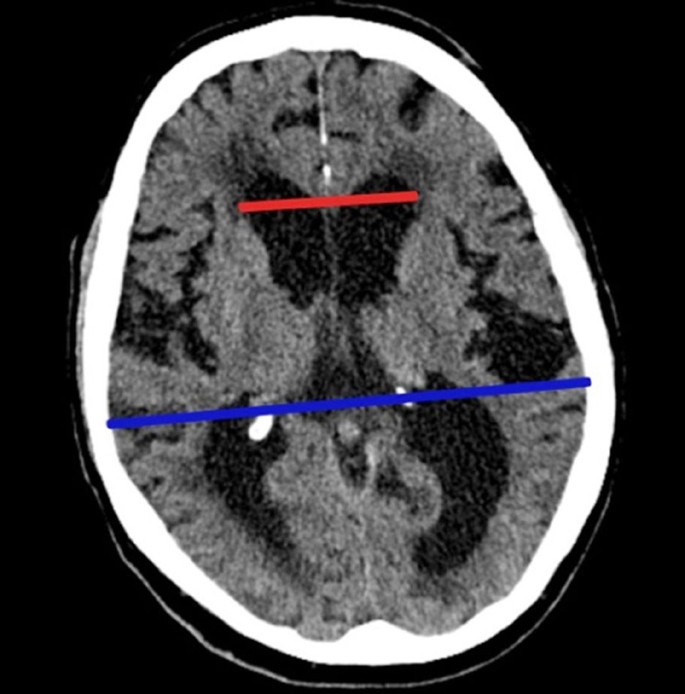

Abb 4 61 Jahrige Patientin Mit Schleichender Demenzieller